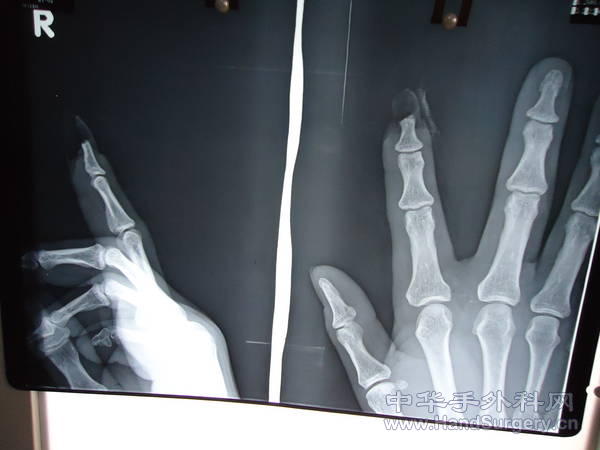

患者为一中年男性,右手食指末节被水泥管挤压离断行临指皮瓣修复术